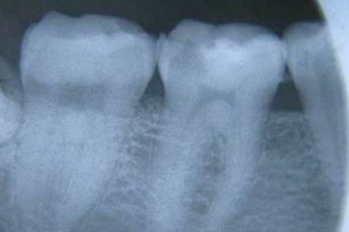

蛀牙(decayed teeth)专业名称叫龋齿(caries),是牙体产生的一种慢性炎症疾病,牙齿表面的细菌生物膜与可发酵的碳水化合物底物结合会导致脱矿质并最终形成蛀牙。在全球范围内,有24亿人(约占世界人口的三分之一)有未经治疗的恒牙龋齿。

初期龋到临床形成龋洞一般需数月至数年时间。

龋齿形成的四个阶段